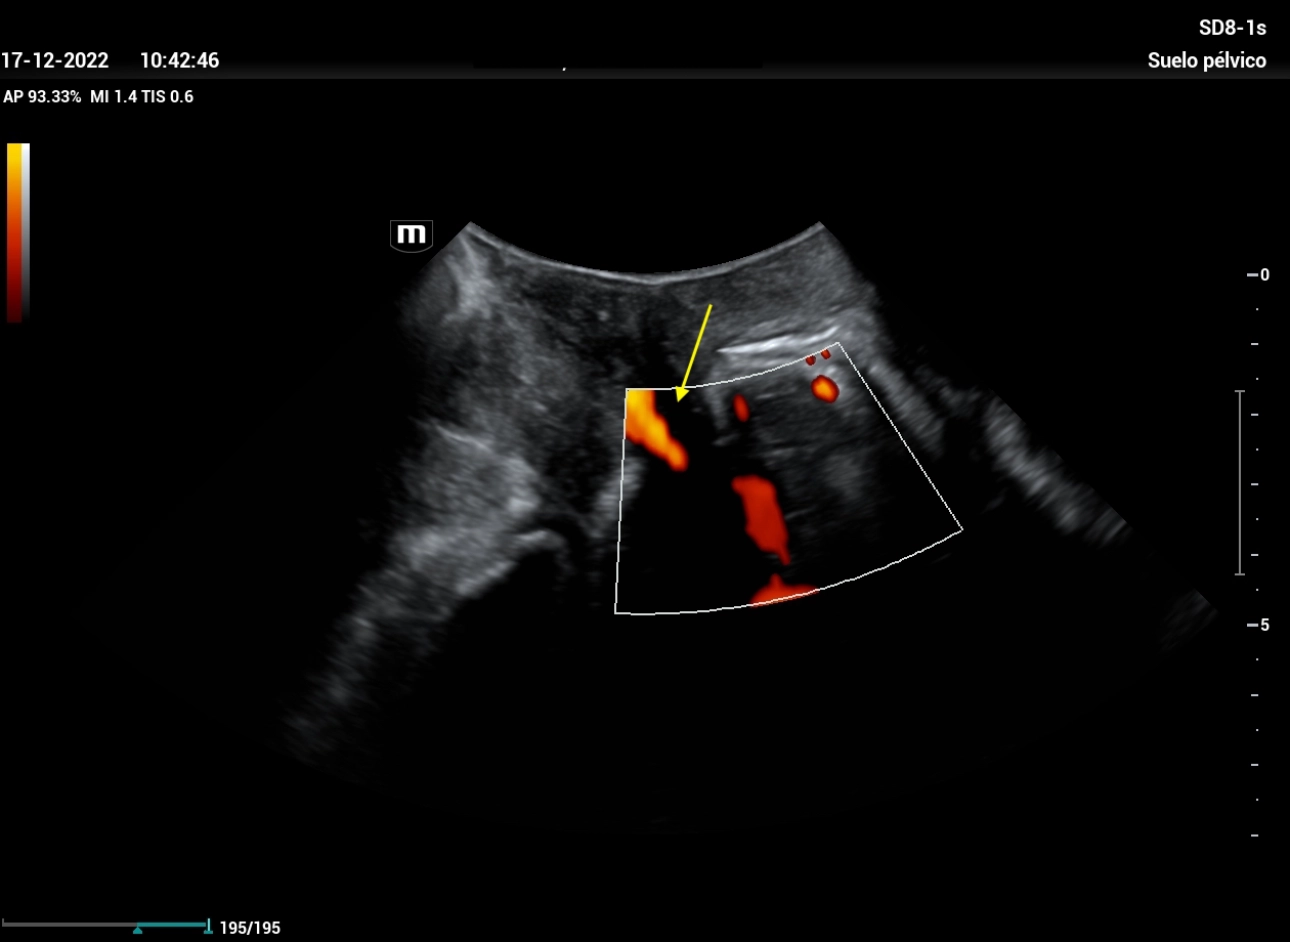

Ultrasound Journal 21 Ultrasound Evaluation of Stress Urine Stress Incontinence Ultrasound Stress urinary incontinence (sui), which refers to involuntary urine leakage due to physical exertion, sneezing or coughing, is the most common type. It helps in differentiating the various. Some people will still have urine. A test that measures the detrusor muscle pressure at rest and during activities like coughing and passing urine. Treatments for stress incontinence often can greatly reduce,. Stress Incontinence Ultrasound.

Ultrasound Journal 21 Ultrasound Evaluation of Stress Urine Stress Incontinence Ultrasound The minimum evaluation before primary midurethral sling surgery in women with symptoms of sui includes the following six. Stress urinary incontinence (sui), which refers to involuntary urine leakage due to physical exertion, sneezing or coughing, is the most common type. Stress urinary incontinence (sui) is the involuntary, sudden loss of urine secondary to increased intraabdominal pressure that is bothersome or. Stress Incontinence Ultrasound.

Ultrasound Journal 21 Ultrasound Evaluation of Stress Urine Stress Incontinence Ultrasound A test that measures the detrusor muscle pressure at rest and during activities like coughing and passing urine. Treatments for stress incontinence often can greatly reduce, and possibly stop, urine leakage. It helps in differentiating the various. Stress urinary incontinence (sui) is the involuntary, sudden loss of urine secondary to increased intraabdominal pressure that is bothersome or affecting the. Some. Stress Incontinence Ultrasound.